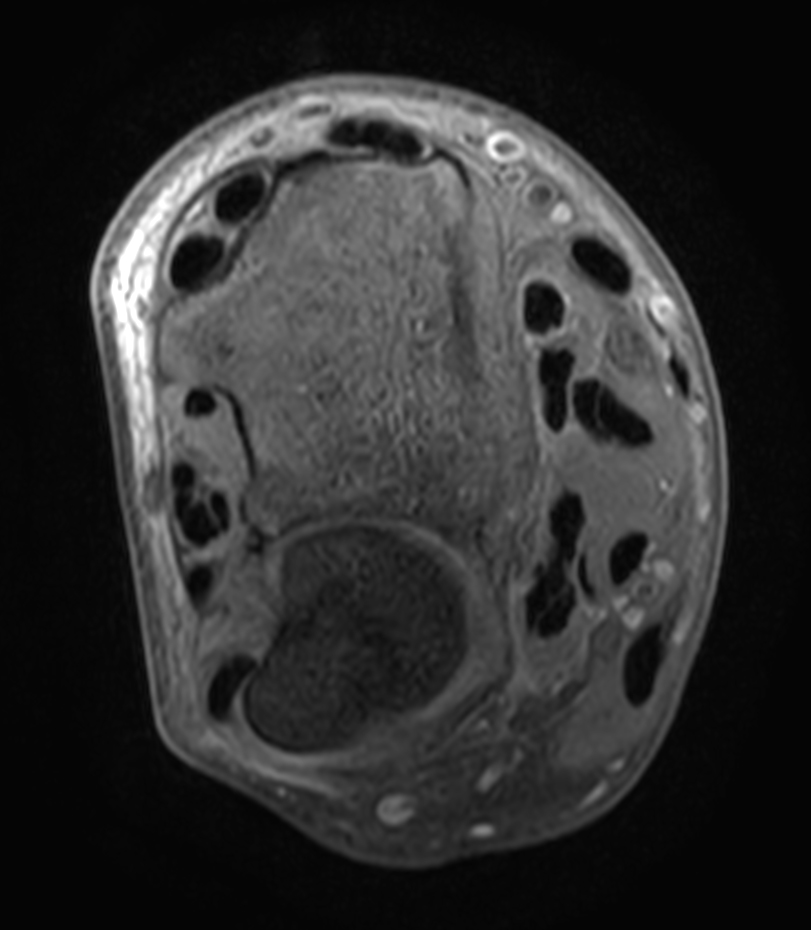

Patient with a wrist fracture. Compressed SENSE is used in all sequences, reducing the scan time while maintain equal image quality compared to scans without Compressed SENSE. 3D sequences have been added to this ExamCard with a comparable in-plane resolution but much thinner slices. Due to the shorter scan times that can be achieved thanks to Compressed SENSE, these 3D sequences could potentially replace the 2D sequences providing more confidence in making the diagnosis.

2D Axial PDw SPAIR